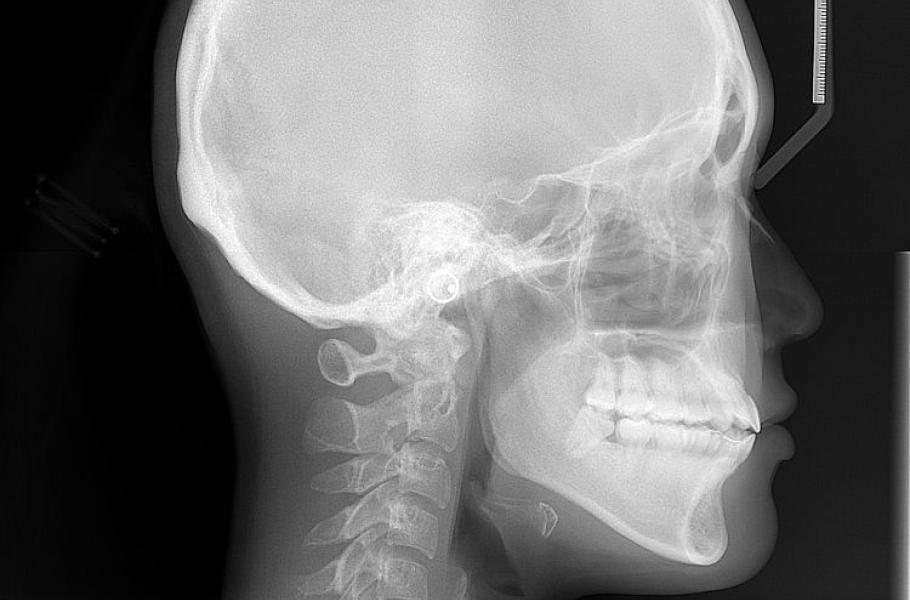

Objev kmenových buněk zodpovědných za růst kostí lebky otevírá nové možnosti v medicíně

Na Univerzitě v Rochesteru řeší vývojové poškození lebky, známé jako kraniosynostóza. Jde o to, že se předčasně uzavře jeden nebo více švů lebky nenarozeného dítěte, což způsobí její deformaci. Postižené děti se vyvíjejí pomaleji a předčasně zpevněná lebka jim stlačuje mozek, což může vést i ke smrti dítěte. Řešením by mohly být kmenové buňky.

Kosti lebky se vyvíjejí jinak, než kosti ve zbytku těla. Mají to na starost jiné kmenové buňky. A až teď se rochesterskému týmu povedlo objevit ty správné kmenové buňky, které jsou zodpovědné za růst lebečních kostí. Za nějaký čas a po nezbytném výzkumu bychom těmito kmenovými buňkami mohli spravovat poškozené lebky.